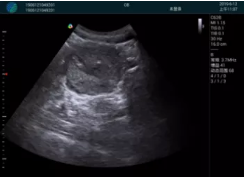

M20查看:囊內(nèi)回聲均勻,邊界清晰,囊壁光滑

M20引導(dǎo)抽吸術(shù)后囊腫消失,原區(qū)域空腔形成,脂肪層與腺體層架構(gòu)發(fā)生改變